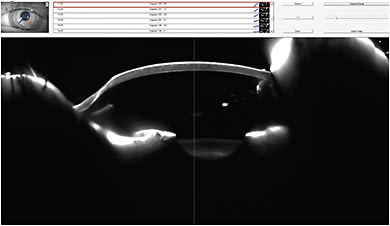

Lens Fitting and Follow-up Care The patient returned for a scleral lens fitting in April 2014. We first determined eye dominance using two different tests, which both confirmed that the patient was right-eye dominant. I diagnostically fit Blanchard OneFit P+A Multifocal lenses in Boston XO in parameters of OD 7.10mm BCR, 14.6mm OAD, –6.25D power and OS 7.20mm BCR, 14.6mm OAD, –5.00D power. Upon application, each lens showed about 280 microns of clearance. After settling, the OD central clearance was 213 microns (Figure 21), and the OS central clearance was 216 microns (Figure 22). With sphero-cylindrical over-refraction, the patient attained 20/20 vision in each eye.

Figure 21. OCT image of the right scleral lens for the patient in Case #6.

Figure 22. OCT image of the left scleral lens for the patient in Case #6.